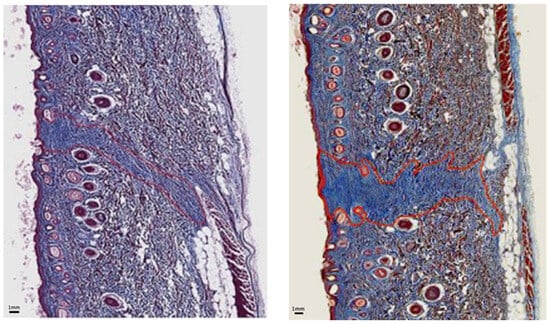

Figure 8 and Figure 9 are representative images of wound histology at 16 days and 2 months post-surgery, respectively. The difference in the amount of scar produced by the EB versus the SB is apparent. In addition, the scar area width is narrower along the incision made with the EB in comparison with that corresponding to the SB.

Figure 9.

Scar histology 2 months post-surgery: Histological sample stained with trichrome at 2 months post-surgery showing less scarring in region of EB skin incision (left) than SB skin incision (right).